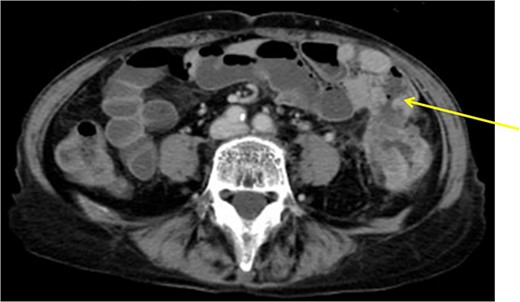

The patient was a 61-year-old woman presenting to our institution with the chief complaint of abdominal distension and diarrhea for a month. Colonoscopy showed descending colon cancer with all circumference-related stenosis. Her laboratory findings revealed a serum CEA level of 5.5 μg/ml and serum CA19-9 level of 778.4 U/ml. The CT scan results showed wall thickening in the descending colon. The descending colon on the proximal side of the tumor was dilated. The ileum is in contact with the tumor. Positron emission tomography (PET-CT) showed fluorodeoxyglucose (FDG) accumulation in the descending colon, mediastinal lymph nodes, enlarged mesenteric lymph nodes, and pararenal aortic lymph nodes (Fig. 3). The patient was preoperatively diagnosed as Stage IV, but she had obstructive symptoms, so surgery was planned. Laparotomy with left hemicolectomy and partial small bowel resection were performed. The ileum, including lymph node dissection around the fistula formation, was also resected.

Descending colon with circumference tumor and small intestine invasion.